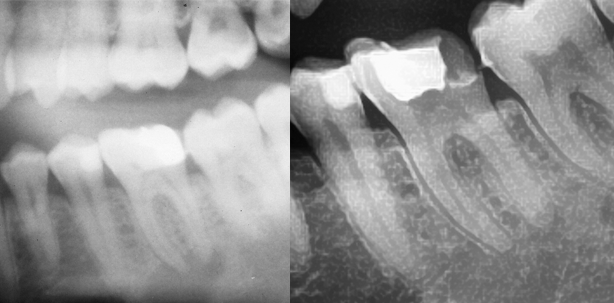

Der Zahn 36 wurde im Notdienst nach vollständiger Entfernung der Restauration (F3 odli) trepaniert, kurz instrumentiert und mit einer medikamentösen Einlage und provisorischem Verschluss versorgt. Es konnte ein dumpfer Perkussionsschall ausgelöst werden. Der Patient hatte keine Aufbissprobleme, ebenso konnte auf Druck im apikalen Bereich dieses Zahnes kein erhöhtes Schmerzempfinden ausgelöst werden; die Beweglichkeit war nicht erhöht. Die zirkulären Taschentiefen waren unauffällig, ein Fistelgang war nicht vorhanden. Die im Notdienst angefertigte Röntgenaufnahme zeigte eine ausgeprägte apikale Parodontitis am Zahn 36 (Abb. 1a und b). Die Diagnose war eine primär endodontische Läsion. Der Patient wünschte unbedingt den Erhalt des Zahnes, trotz des ausgedehnten röntgenologischen Befundes.

Abb. 1a und 1b